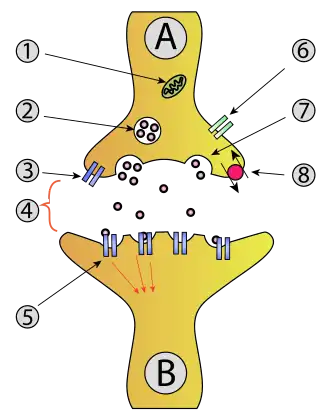

SLC7A11 plays an important role in glutathione production throughout nervous and non-nervous tissues. In the nervous system, SLC7A11 regulates synaptic activity by stimulating extrasynaptic receptors and performs nonvesicular glutamate release. This gene is highly expressed by astrocytes and couples the uptake of one molecule of cystine with the release of one molecule of glutamate. The expression of Xc- was detected throughout the brain with higher expression found in the basolateral amygdala, the retina and the prefrontal cortex. The inhibition of system Xc- has been found to alter a number of behaviors, which suggests that it plays a key role in excitatory signaling.

SLC7A11 is a member of a heterodimeric Na+-independent anionic amino acid transport system highly specific for cystine and glutamate. This antiporter imports cystine and exports glutamate, which are both amino acids. An antiporter functions with a one-to-one counter-transport, which is when one substance is transported across the membrane at the same time another substance is transported across the membrane in the opposite direction. The antiporter is a heterodimeric amino acid transporter, requiring both the SLC7A11 light chain and SLC3A2 heavy chain linked by a disulfide bridge.[8] The SLC7A11 light chain has 12 transmembrane domains consisting of 501 amino acids, and the SLC3A2 heavy chain appears to be highly conserved among transporters. The human SLC7A11 has an 89% similarity of amino acids to the homologous mouse xCT protein. The complementary DNA, cDNA, has a total of 9648 base pairs. The SLC7A11 gene has been found not only in the brain, but has also been found to be expressed in the spinal cord, pancreas, and in glioma cells.[9][10]

There are many mechanisms that exist to regulate the expression of system Xc-, although it is not the sole determinant of extracellular glutamate or intracellular glutathione. An example is amino acid deprivation, which triggers up regulation of the transporter. A key regulator is extracellular glutamate; when it becomes excessive, it goes from an excitatory transmitter to an excitotoxin.[9] The inhibition of uptake of extracellular cystine into cells leads to decreased levels of intracellular glutathione which leads to ferroptosis.[11][12] This regulation may be done through Excitatory Amino Acid Transporters (EAATs), which decrease extracellular glutamate and increase intracellular glutamate in astrocytes. When looking at its structure, xCT seems to be the main determinant for the system's activity. Glutamate and cystine can be transported in both directions, but, generally, more cystine is imported and more glutamate is exported. Extracellular glutamate acts as a competitive inhibitor for cystine uptake via system Xc-.[13]

There is a high amount of glutamate in mammalian cells. Glutamate is necessary for excitatory signaling between neurons. The release must be highly organized, due to the large amounts of glutamate at the synaptic cleft, and the fact that it is released at high speeds. This mechanism of release at the synaptic cleft is partially controlled through the active transport of glutamate out of astrocytes by system Xc-. This release also has a physiological role in the regulation of glutamatergic metabotropic receptors and control of other neurotransmitters.[10]

It has been found that cocaine produces a decrease in Cystine-Glutamate exchange via system Xc-, leading to a decrease in basal, extra synaptic glutamate levels in the nucleus accumbens core (NAcc) region of the brains of cocaine-withdrawn rats. It has also been observed in withdrawn rats that a decrease in Group 2 mGluR inhibition of vesicular release, most likely due to the decrease in extrasynaptic glutamate levels, leads to an increase in cocaine-evoked glutamate signaling in their NAcc.[15] An infusion of cysteine in the NAcc of withdrawn rats leads to an increase in extrasynaptic glutamate, near the levels of the control rats, and prevents an increase in synaptic glutamate signaling after a cocaine injection. These findings suggest there is a decrease in system Xc- activity in cocaine-withdrawn rats. It has also been found that cocaine increases glutamate signaling in the synaptic cleft, further supporting this conclusion.[15]

Administration of the cysteine prodrugs N-acetylcysteine or L-2-oxothiazolidine-4-carboxylate blocks cocaine reinstatement in rats.[15] N-acetylcysteine has been shown to decrease drug-seeking behavior for nicotine and heroin as well. However, N-acetylcysteine does not alter the cocaine-induced rush or euphoria; it only causes a reduction in drug-seeking behavior. N-acetylcysteine works by increasing levels of cysteine in cells, leading to an increase in system Xc- activity. This increase in system Xc- activity leads to an increase in extrasynaptic glutamate, causing stimulation of Group 2 mGluRs and an inhibition of synaptic release of glutamate. Cysteine prodrugs also lead to an increase in antioxidant properties by increasing levels of glutathione. Increased levels of glutathione lead to a lower toxicity of methamphetamine and alcohol, and cause a decrease in tumor formation after chronic smoking.[15] N-acetylcysteine has been shown to decrease cravings and use of cocaine and tobacco, as well as other compulsive behaviors such as gambling and trichotillomania.[15]

It has been proposed that schizophrenia may be due to an increase or a decrease in glutamate signaling, leading to abnormal excitatory signaling in the prefrontal cortex region of the brain.[15] Glutamate release by astrocytes has been linked to the synchrony of neurons in the hippocampus and cortex. A decrease in system Xc- activity may result in an increase in synaptic glutamate and a decrease in extrasynaptic glutamate. Administration of N-acetylcysteine leads to an increase in extrasynaptic NMDA receptor activation, suggesting that glutamate released from system Xc- may cause the activation of extrasynaptic NMDA receptors. A decrease in system Xc- activity may cause a decrease in the activation of extrasynaptic NMDA receptors due to either a decrease in extrasynaptic Glutamate levels or a decrease in glutathione levels after the decrease in cystine transport. On the other hand, a decrease in system Xc- activity may lead to an increase in the activation of synaptic NMDA receptors due to the decrease in activation of Group 2 mGluRs. A decrease in nonvesicular release of glutamate leads to an increase in expression of postsynaptic glutamate receptors, such as NMDA receptors. A disruption in nonvesicular glutamate release may affect synapse formation, lead to altered release of neurotransmitters, and could even disturb cortical migration during development. All of these seem to be associated with schizophrenia.[15]